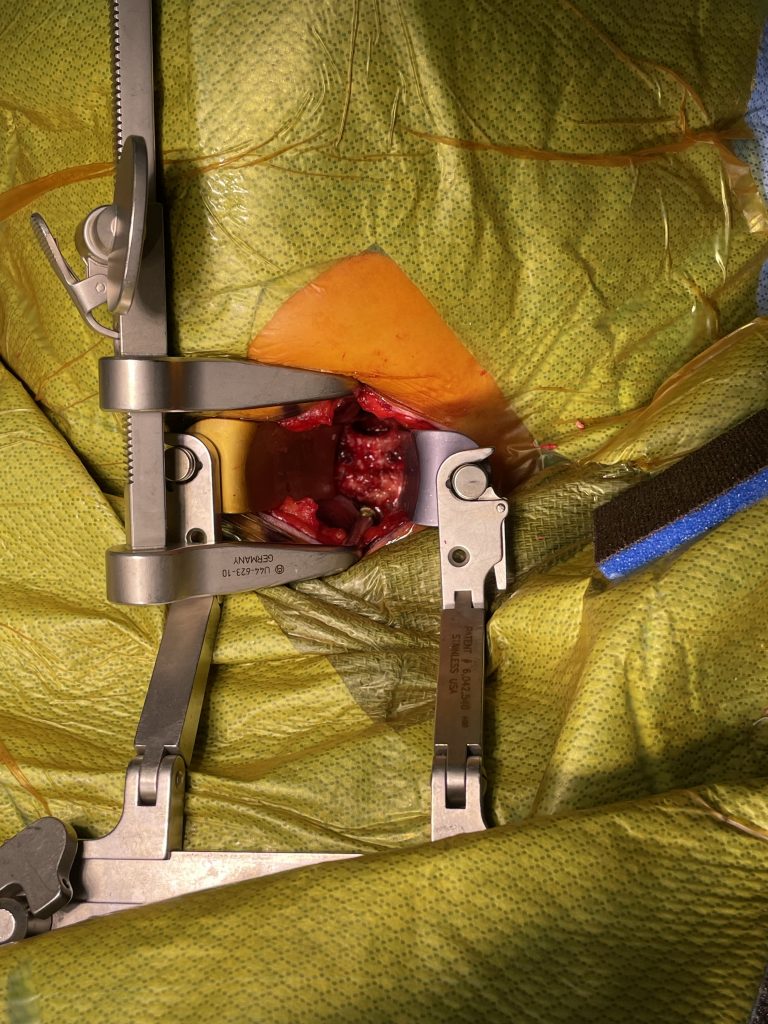

Fig 3: Intraoperative photo showing a deep exposure with deep retractors to access the anterior cervical spine